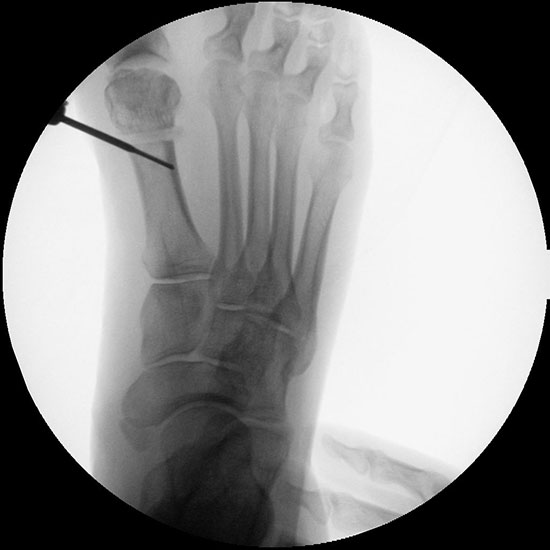

Instrumentarium für die minimalinvasive Vorfußkorrektur.

Abbildung 3

• Fräse für Minimalinvasive Fußchirurgie (Drehzahl: ca. 350 RPM, Drehmoment >50 N/cm).

• Shannon Fräser 20 mm, 2.0 mm Durchmesser.

• Shannon Fräser 12 mm. 2,0

• Bildverstärker.

• Beaver-Blade Messer.

• Mini-Raspatorium.

• Kanülierte Schrauben bis 60 mm Länge.

• Bohrmaschine.

• Kirschnerdrähte mit 1,2 mm (temporäre Fixation) und 2,4 mm (Reposition), special elevator.